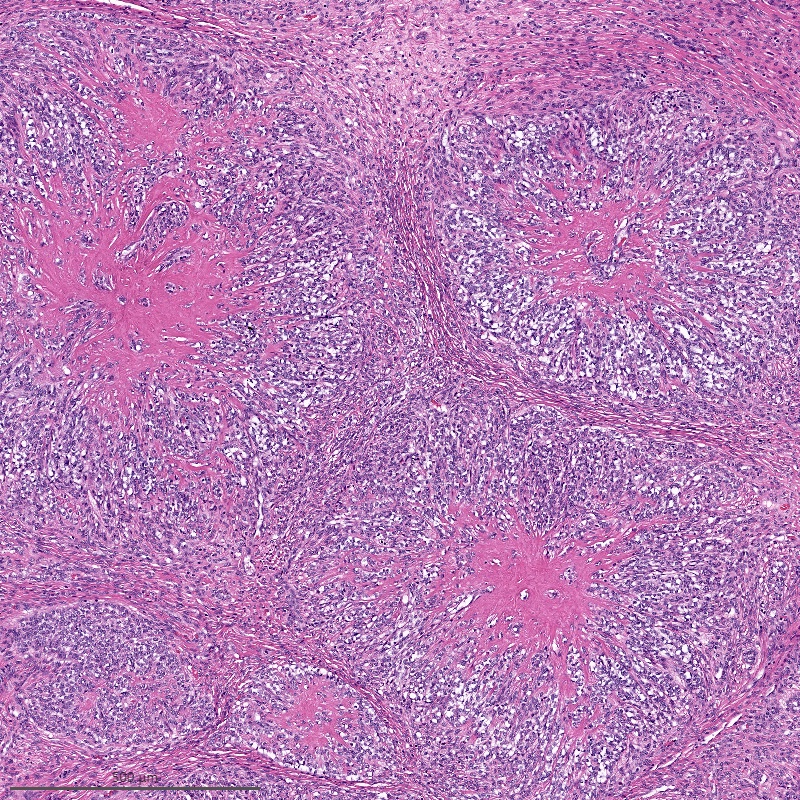

Microscopic (histologic) description

- Irregular cellular islands, forming permeative tongue-like pattern of myometrial invasion with frequent vascular invasion

- Monotonous oval to spindle cells with minimal cytologic atypia, vesicular chromatin and scant cytoplasm

- Mitotic count is usually low (< 5/10 high power fields), necrosis is usually absent

- Tumor cells may whorl around delicate arteriolar type vessels, reminiscent of proliferative phase endometrial stroma

- May have admixed collagen bands / plaques and foamy histiocytes

- May have smooth muscle differentiation, particularly in a starburst morphology, with collagen bands radiating towards the periphery of the nodule

- Other reported types of differentiation: fibromyxoid / fibrous, sex cord-like, epithelioid, rhabdoid, endometrioid glands, pseudopapillae, clear cells, bizarre cells, adipose tissue (Mod Pathol 2016;29:S92)

Microscopic (histologic) images

Contributed by Elizabeth Kertowidjojo, M.D., Ph.D., M.P.H. and Ayse Ayhan, M.D., Ph.D.